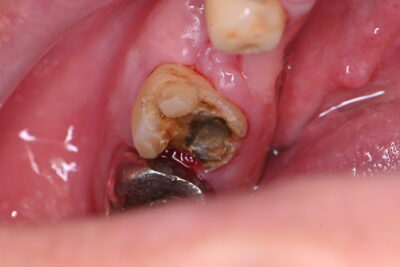

Before⇩

左下6番

銀歯が外れて、中は黒く虫歯になっていました。